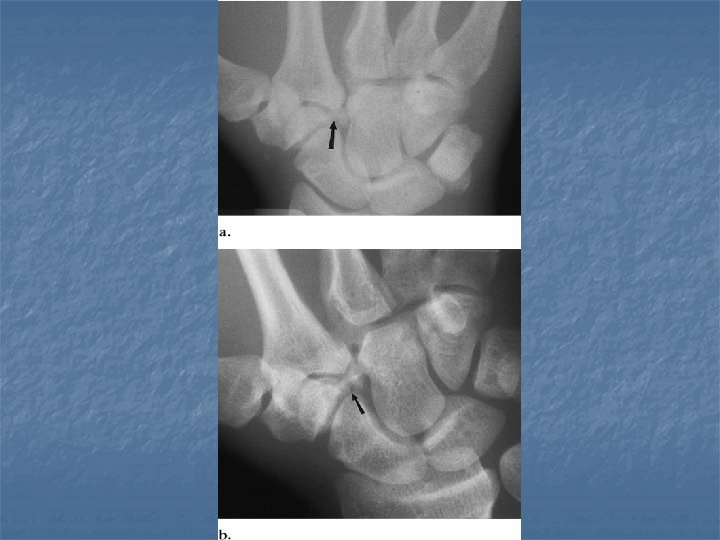

Scaphoid fracture n n Most common carpal bone to be fractured Age 15 -30 Fall on outstretched arm Classification Distal pole and tubercle 5 -10% n Proximal pole 15 -20% (nonunion & AVN) n Waist 70 -80% n

Scaphoid fracture

PA PA with ulnar deviation